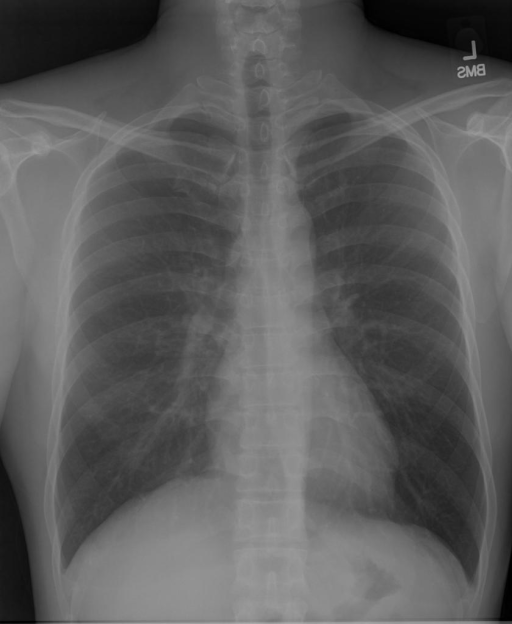

In this work, we developed computer-aided diagnosis system that can automatically detect thoracic diseases present in Chest X-rays. Specifically, we developed a multi-head self-attention convolutional network based multi-label classification framework for predicting the presence of common thoracic diseases on four of the largest publicly available chest X-ray datasets, namely, ChestX-ray14, CheXpert, MIMIC-CXR-JPG, and IU-CXR. Fig. 2 shows sample chest X-ray from four datasets having positive cardiomegaly. The block diagram of our proposed model for the identification 111We will use the term identification and classification interchangeably. of common thoracic diseases is shown in Fig. 1.

(a) ChestX-ray14

Refer to caption

(b) CheXpert

(c) MIMIC-CXR-JPG

(d) IU-CXR

Figure 2: Randomly sampled chest X-ray having Cardiomegaly from each of the four datasets: ChestX-ray14, CheXpert, MIMIC-CXR-JPG, and IU-CXR.